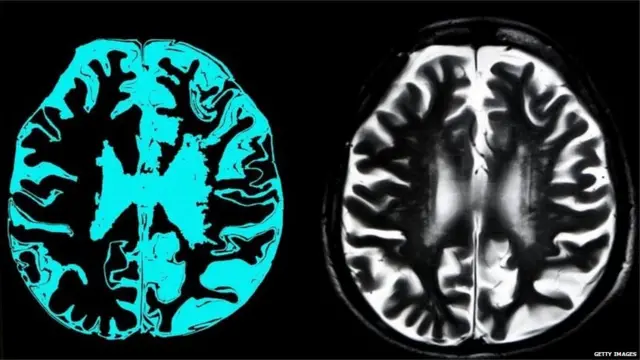

मानसोपचारतज्ज्ञ आणि न्यूरोलॉजिस्ट या रोगाचं निदान करतात. आजाराचं निदान करण्यासाठी एक प्रश्नावली असते. त्या प्रश्नाची उत्तरं घेतली जातात. त्यावरून एखाद्याला डिमेंशिया आहे का, हे शोधता येतं. याशिवया, MRI करूनही या आजाराचं निदान करतात.

या आजाराविषयी सांगताना डॉक्टर सागर मुंदडा सांगतात, "अल्झायमर्समध्ये जसजसं वय वाढतं तसा मेंदूचा आकार लहान होत जातो. मेंदुतल्या वळ्या कमी होत जातात. यामुळे विसरभोळेपणा येतो. अल्झायमर झालेल्या व्यक्तींना काही तासांपूर्वी घडलेल्या गोष्टींचा विसर पडतो."